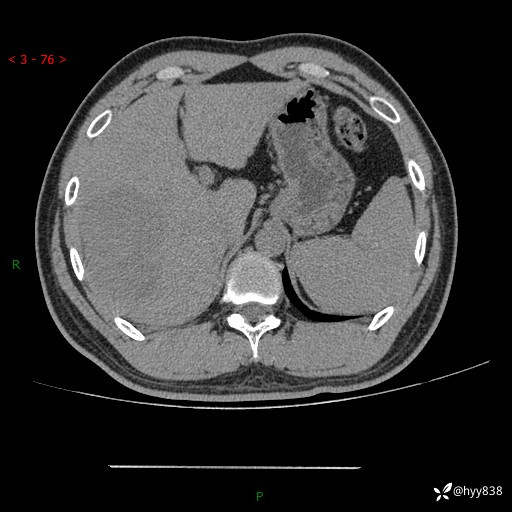

肝脏CT平扫

img